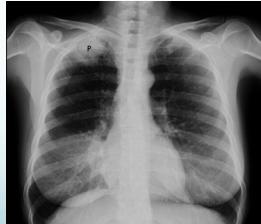

Associated Findings:

- Horner’s syndrome (indicative of proximal root avulsion):

- Ptosis: Drooping of upper eyelid

- Miosis: Constriction of pupil

- Enophthalmos: Sunken appearance of eyeball

- Anhydrosis: Absence of sweating on affected side